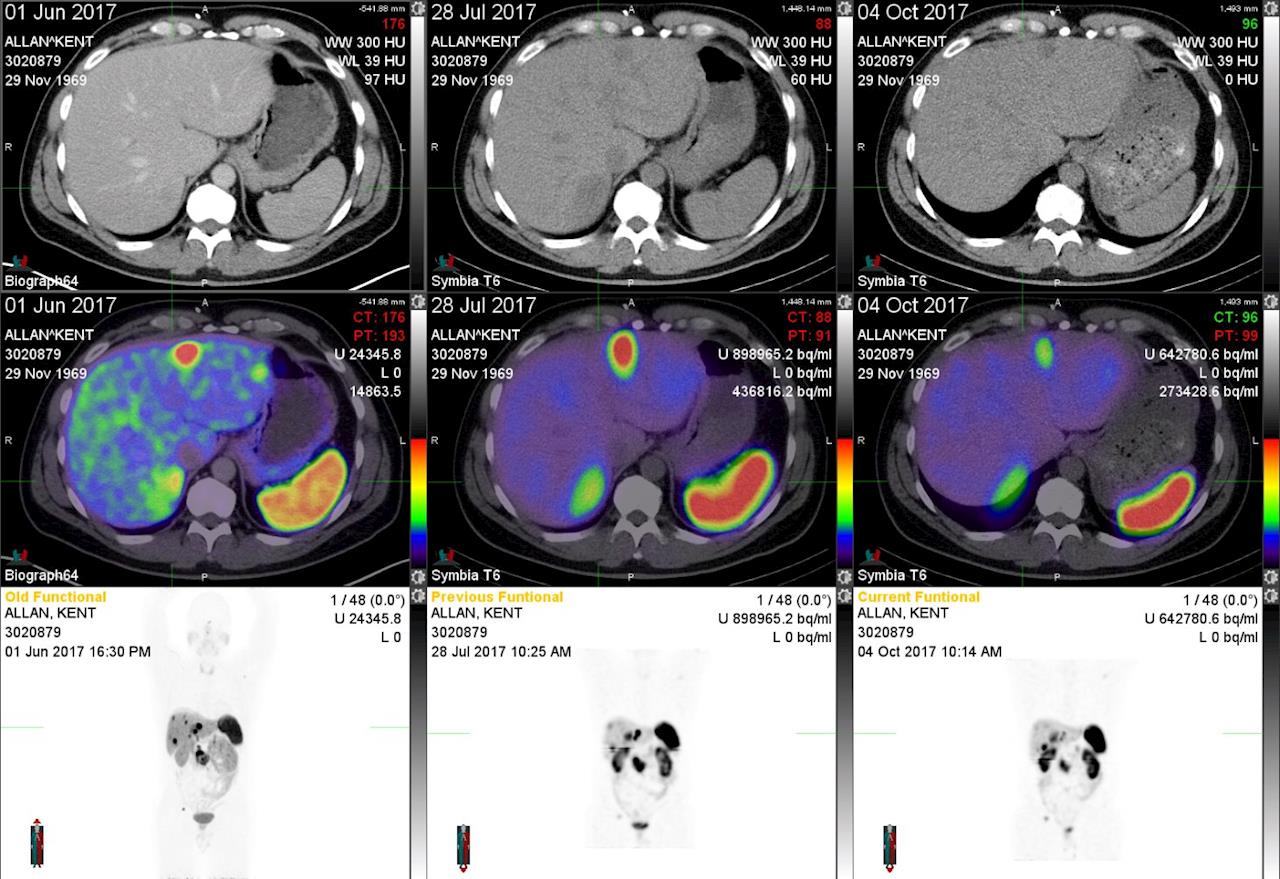

I'm trying to upload a scan so you can see the changes after each treatment.

in 2015 his cancer cells transferred to the liver, pancreas and other parts. He had been told from the doctor that he may only have about two years to live. The new scan in April this year found that the tumors had quadrupled in size only 1 year after the last scan, and he needs to travel to Melbourne to have further treatment to extend his live. This treatment is called Peptide Receptor Radionuclide Therapy (PRRT), the cost is about $50,000 and is known to prolong life by 5 years.

2015年他的癌细胞转移到了肝,胰腺等部位,医生告知他的生命也许只有两年左右。今年四月的扫描发现他的那些肿瘤数量比一年前翻了两番。他需要到澳大利亚墨尔本去做一种特殊的治疗来延长他的生命。这种治疗称为肽受体放射性核素治疗(PRRT),费用大约是5万元,但已知可将生命延长大约5年。

I have had success in shrinking my tumors easing alot of pain but unfortunately not all.

Professor says it will never make things operable but will buy me time.

So an update of treatment so far ...i have had 2 of 4 treatments and after the new year will be going back for the last 2 maybe more pending results.